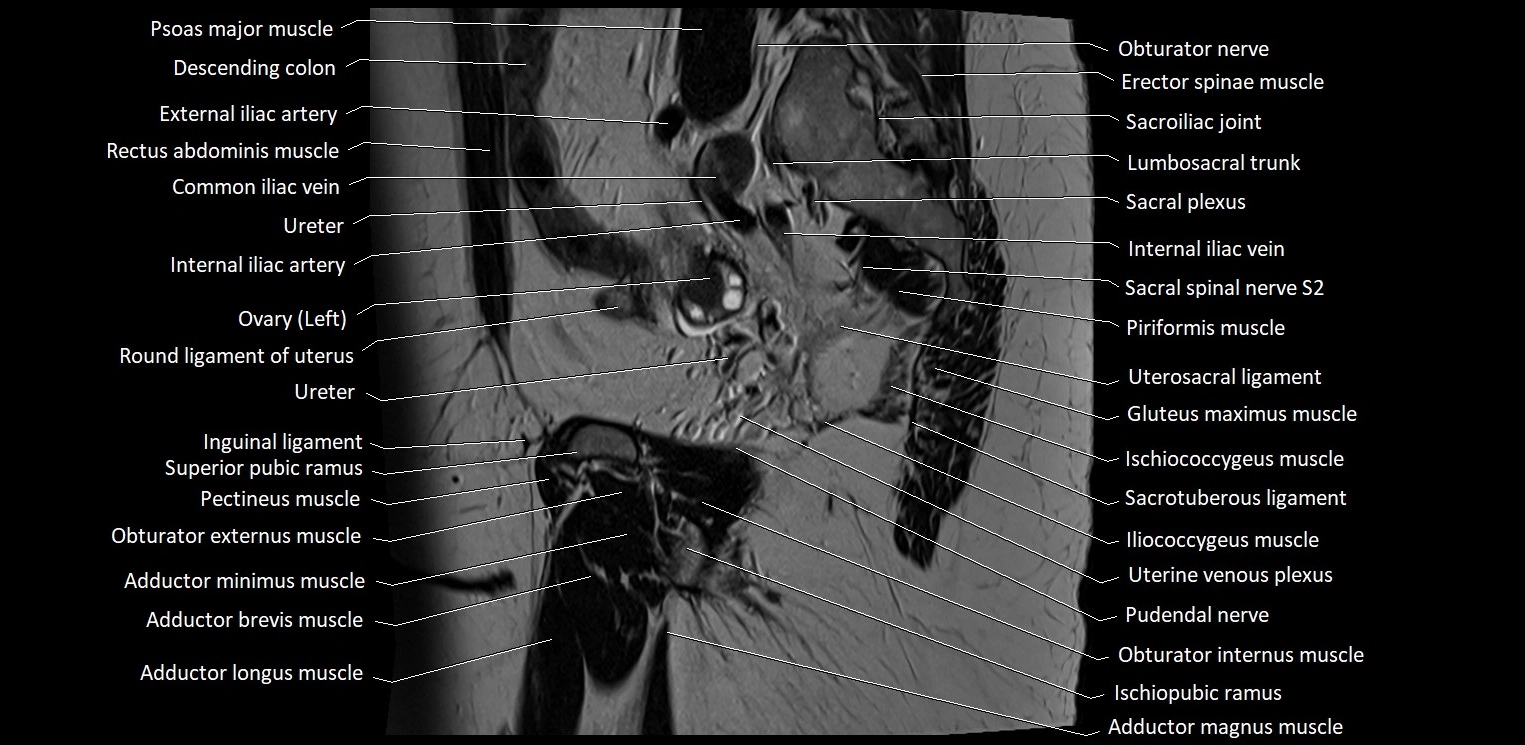

- Adductor brevis muscle

- Adductor longus muscle

- Adductor magnus muscle

- Adductor minimus muscle

- External iliac artery

- Femoral nerve

- Gracilis muscle

- Head of femur

- Ileum

- Iliococcygeus muscle

- Inguinal ligament

- Internal iliac artery

- Internal iliac vein

- Ischiococcygeus muscle

- Ischiopubic ramus

- Lumbosacral trunk

- Marginal artery of Drummond

- Obturator externus muscle

- Obturator internus muscle

- Obturator nerve

- Pectineus muscle

- Piriformis muscle

- Psoas major muscle

- Pudendal nerve

- Sacral plexus

- Sacroiliac joint

- Sacrotuberous ligament

- Sciatic nerve

- Spinal nerve L5

- Spinal nerve S2

- Superior pubic ramus

- Suspensory ligament of ovary

- Uterine venous plexus

- Uterosacral ligament